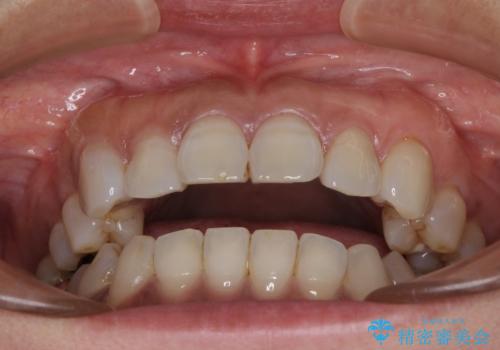

極端な上下前歯の開咬を改善 オープンバイトのインビザライン矯正

- 上下前歯の隙間を気にして来院された患者様です。

開咬の治療は、前歯を閉じるように動かすとともに、上下臼歯を圧下(骨内にめり込ませる)させることで進めて行きます。